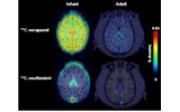

血中の異物や薬物から脳を守る機能は成長とともに発達し、幼少期には脳に取り込まれやすい薬物が存在することを、理化学研究所らが世界で初めて霊長類(アカゲザル)で確認した。理研分子イメージング科学研究センター 分子プローブ動態応用研究チーム高島忠之研究員と、同分子プローブ機能評価研究チーム尾上浩隆チームリーダー、東京大学大学院薬学系研究科との共同研究の成果という。

抗不整脈薬のベラパミルでは2.3倍、未成年者の副作用が指摘されている抗インフルエンザ薬のタミフルでは約1.3倍、幼少期のサルでは成熟したサルに比べて速く脳へ取り込まれることがわかったという。